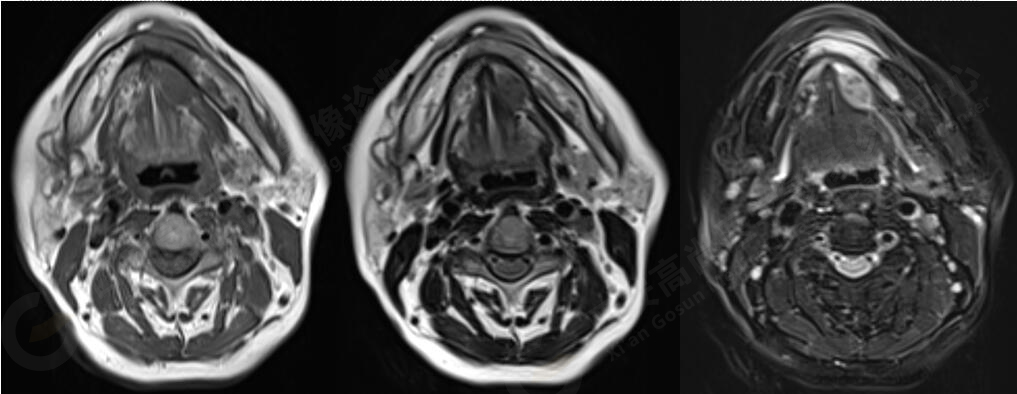

MR平掃+增強(qiáng):左側(cè)口底部下頜骨周圍見大小約3.4cmX3.3cmX3.3cm的團(tuán)塊狀稍長(zhǎng)T1稍長(zhǎng)T2信號(hào),壓脂像上呈稍高信號(hào),病灶邊緣清晰,形態(tài)不規(guī)則,下頜骨骨質(zhì)破壞,強(qiáng)化掃描示:左側(cè)下頜骨周圍病灶呈不均勻明顯強(qiáng)化,邊緣強(qiáng)化為著。

此腫瘤位于左側(cè)口底部下頜骨周圍,未見明顯囊變,下頜骨骨質(zhì)破壞,DWI像上病灶呈明顯低信號(hào),ADC圖上呈低信號(hào),增強(qiáng)后不均勻明顯強(qiáng)化,病人年齡較大,可以考慮惡性腫瘤,口底好發(fā)鱗癌。